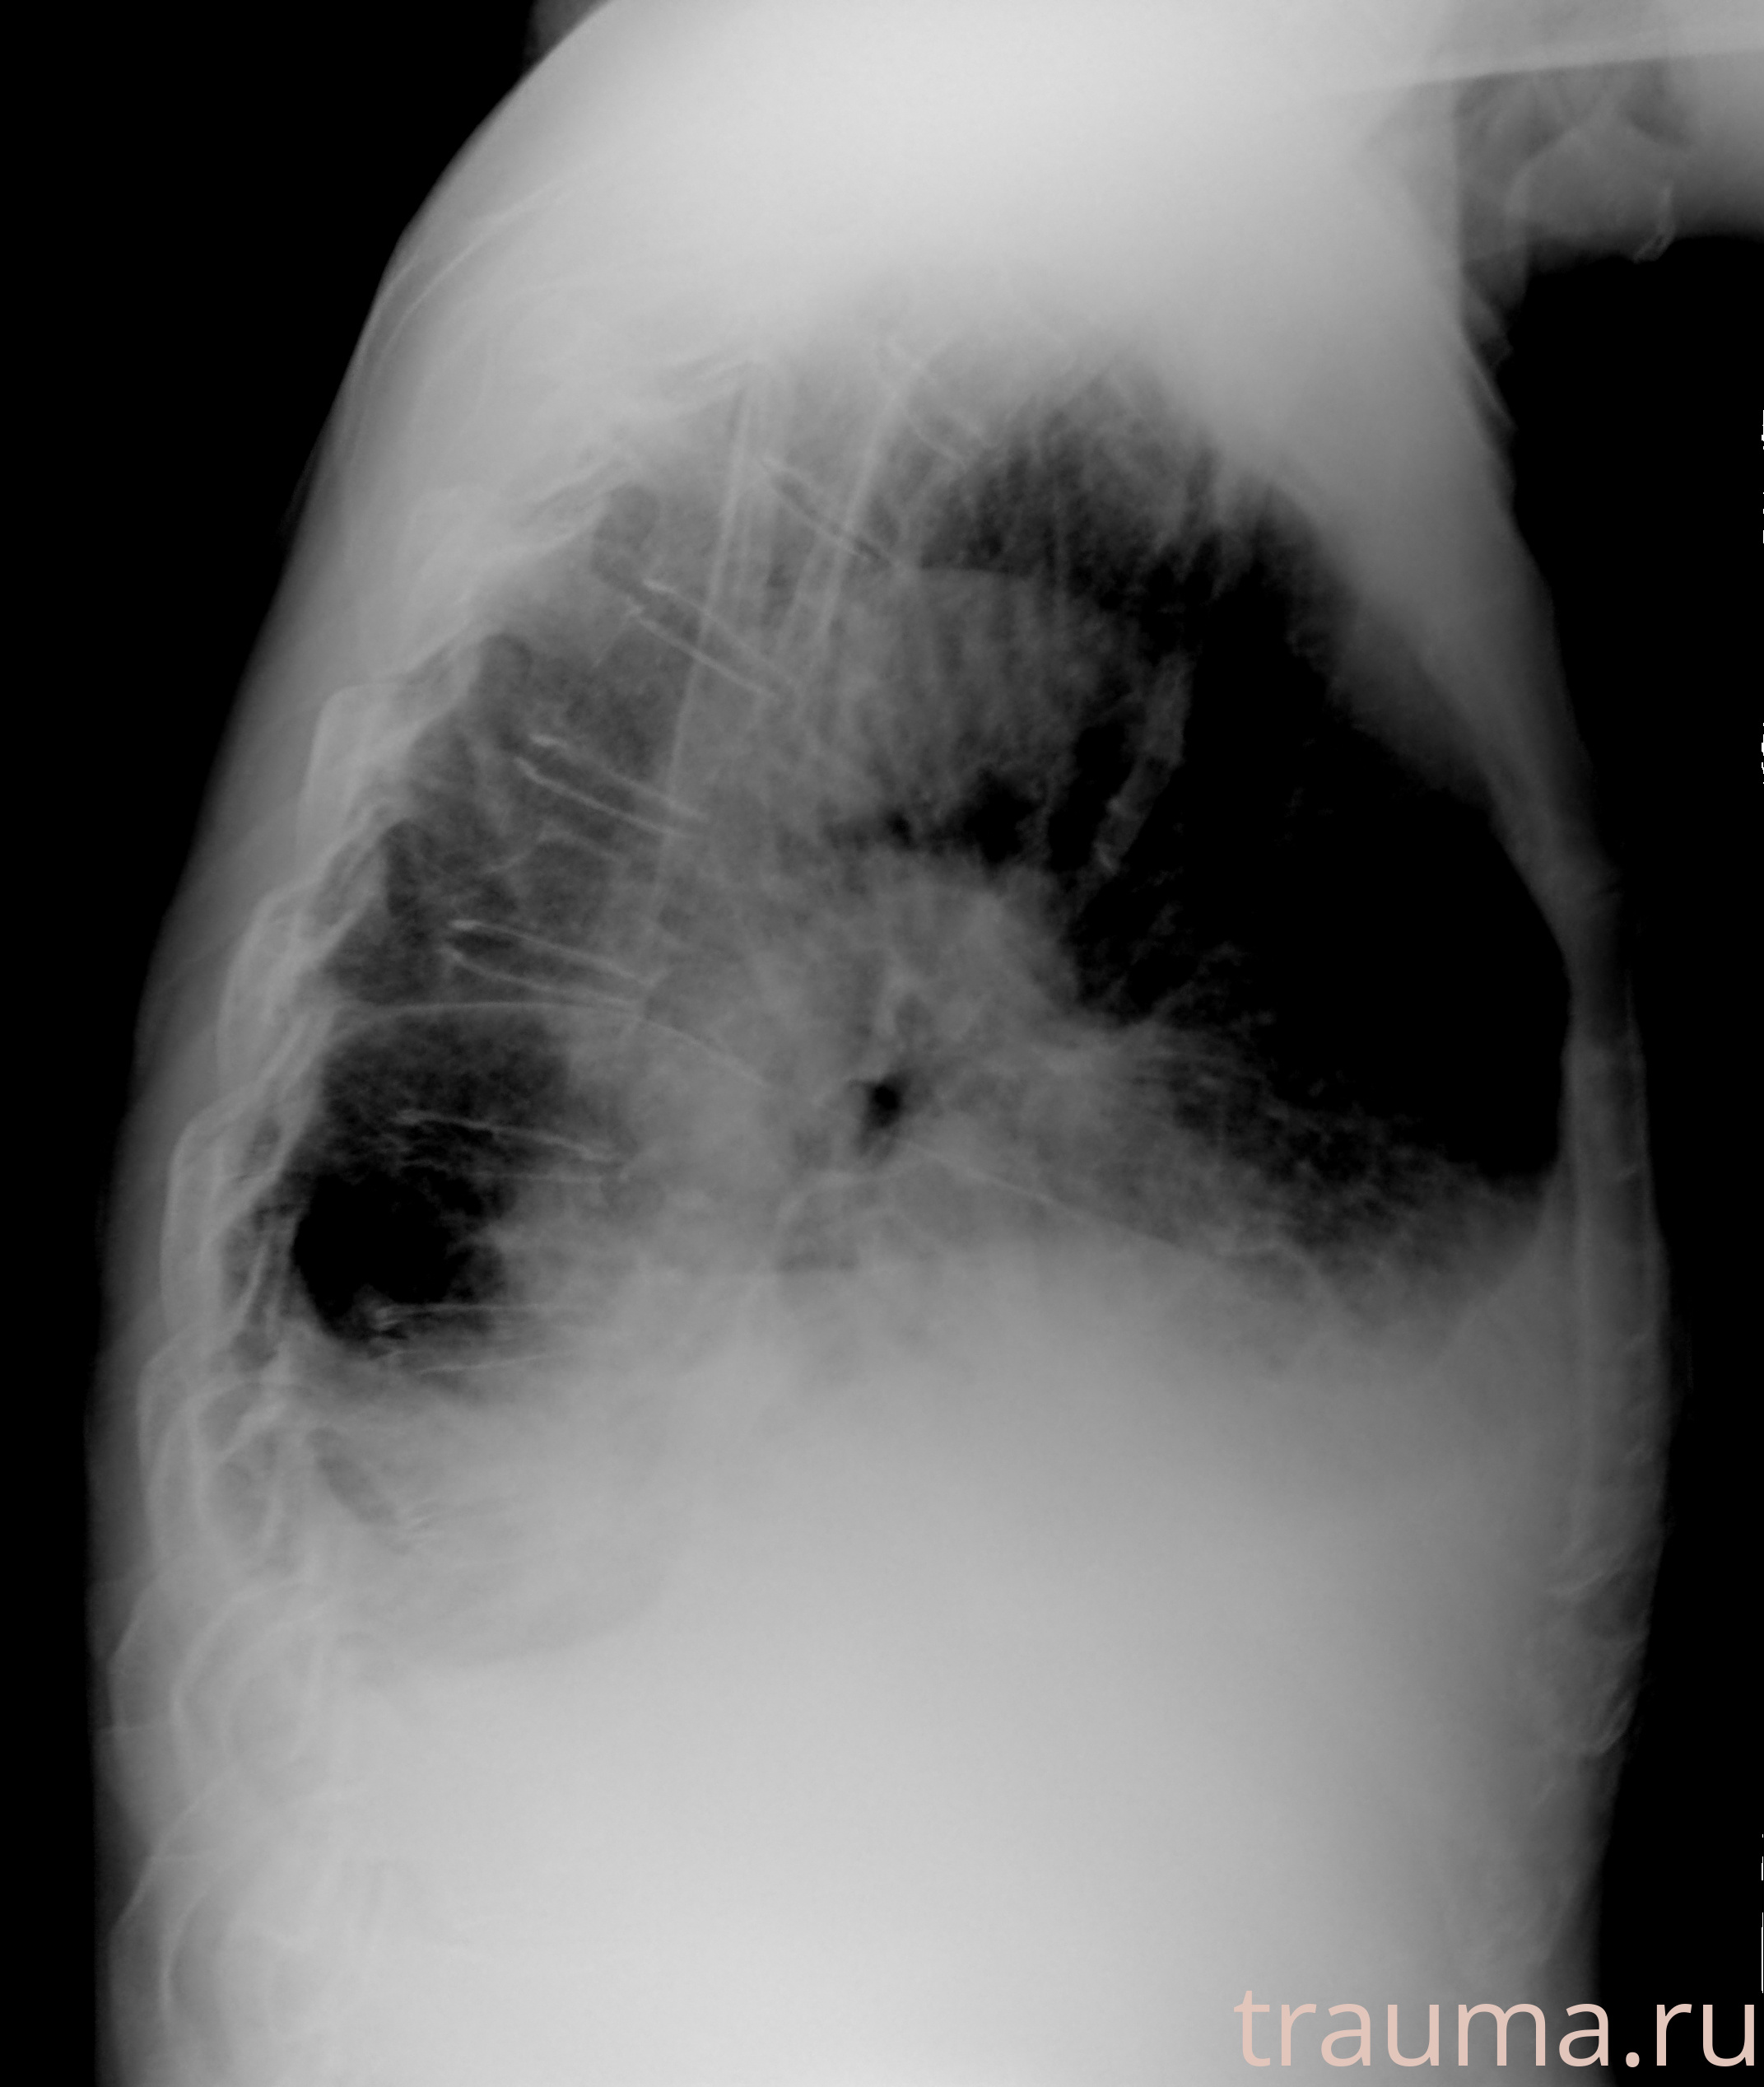

Рентгенограммы

Рентген на дому: по вашему адресу приезжает врач-рентгенолог, травматолог-ортопед с мобильным рентгеновским аппаратом, проводит диагностику травмы или заболевания, делает необходимые рентгенограммы, дает рекомендации по дальнейшему лечению. Получить качественные снимки в домашних условиях возможно благодаря уникальной методике, разработанной МосРентген Центром для института  Склифосовского

при переломе шейки бедра и пневмонии от компании МосРентген Центр - партнера Института имени Склифосовского